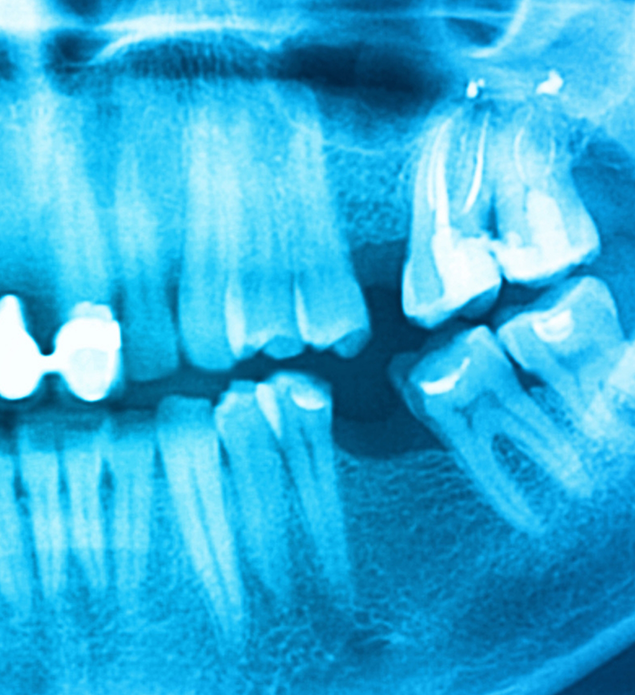

Reasons Why Tooth Extractions Are Necessary

Here are a few reasons our Sparks dental team may recommend having a tooth extracted:

- Severe decay or damage that has destroyed too much of the tooth for a dental crown or other restoration to repair it.

- In preparation for orthodontic alignment especially when there is severe crowding of teeth.

- In preparation for the design and crafting of a partial or full denture.

- When damage or decay may adversely affect surrounding teeth, gums, or oral structures.

- There isn’t adequate space for the third molars (wisdom teeth).